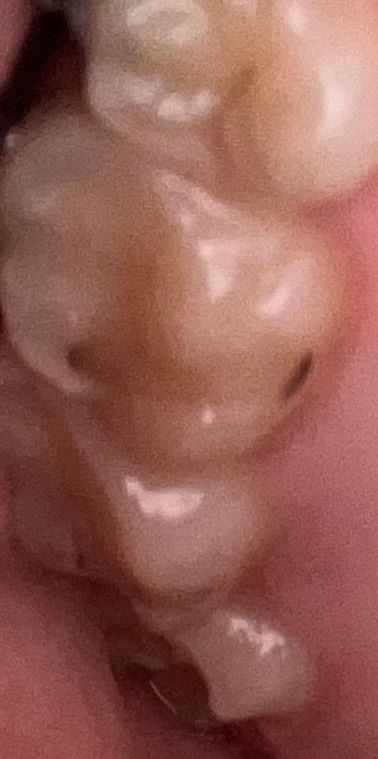

치아 옆면에 충치가 있었던거 같은데 교정장치를 붙여주셨어요

제가 사진처럼 저렇게 치아 옆면에 충치? 같은게 있었거든요 근데 저렇게 충치? 난 자리에 교정장치를 붙이셨어요

붙이시기 전에 긁어 보는거 같긴 한거 같은데 그냥 툭툭 건드시고 말았거든요? 이거 괜찮은 건가요?

사진에 보이는건 충치라기 보다는 예전에 치료한부위에 미세틈이 생기면서 착색이 생긴거 같습니다.

치아에 검은색으로 보이는 부분은 충치일 수 있지만 단순한 착색이나 충전물 사이에 생긴 착색일 수 있습니다.

이런 경우에는 굳이 제거를 하지 않아도 큰 문제가 생기지 않기 때문에 그렇기 때문에 교정 장치를 붙이는 경우가 있습니다. 자세한 확인을 위해서 치과에서 진료를 받아보세요.

화질이 좋지 않아 정확히는 보이지 않으나 해당 치아는 이전에 레진 등의 재료로 치료를 받았던 흔적이 보입니다. 그 충전물에 변색이 일부 있는 것이고 충치는 아닌 것 같습니다. 긁어서 확인을 해봤다면 아마 충치가 아닌것으로 판단하고 해당 부위에 교정재료를 붙이셨을 것입니다.